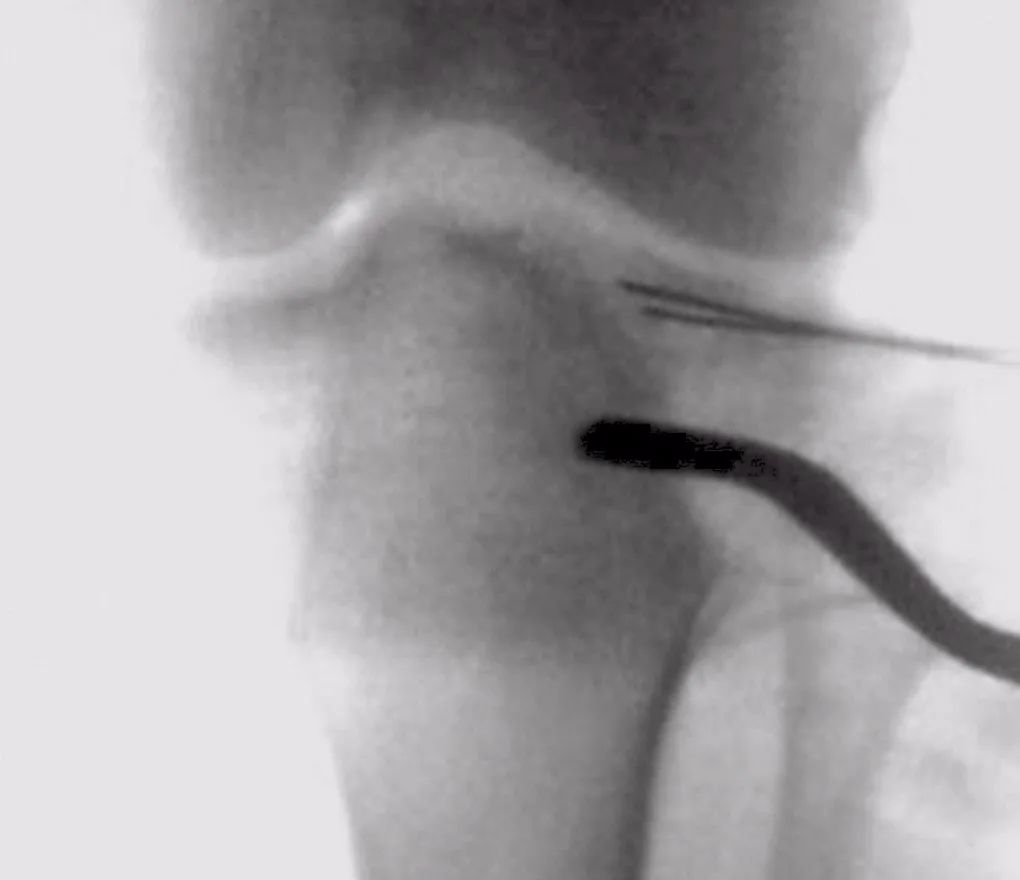

图11 透视下检查关节复位

骨折碎块之间的裂缝可以撬开,可能有助于更清楚地呈现关节内骨折并有助于随后的直接复位(图9)。塌陷的关节内的碎片通常有一个完整的强大的软骨下骨支撑,沉积进入薄弱的下面的松质骨。该凹陷的部分必须在钝骨膜剥离子(Freer)的帮助下,将软骨下骨逐渐抬高。这个高度应该从中心开始,并朝向外围(图10)。周围关节区域的边缘嵌入应该被发现和纠正。外周变缘或边缘附着的软组织的高度往往处于正常水平,而且股骨髁也可用来作为复位的参照。一旦出现骨缺损,骨折块需要使用至少两个1mm克氏针临时固定在软骨下骨,穿过骨折区域到达对侧髁(图11)。在骨质疏松的骨或缺损无法修复的区域,软骨下的腔隙用松质骨或人工骨移植(图12)。一旦关节的表面被解剖修复,骨碎块被替换,用1mm软骨下克氏针重建(图13)。最终修复通过透视确认(图14A和B)。选择合适的支撑钢板,能对提高关节面起到很好的支撑作用,尤其是近端的锁定螺钉能起到类似木筏样的支撑效果。